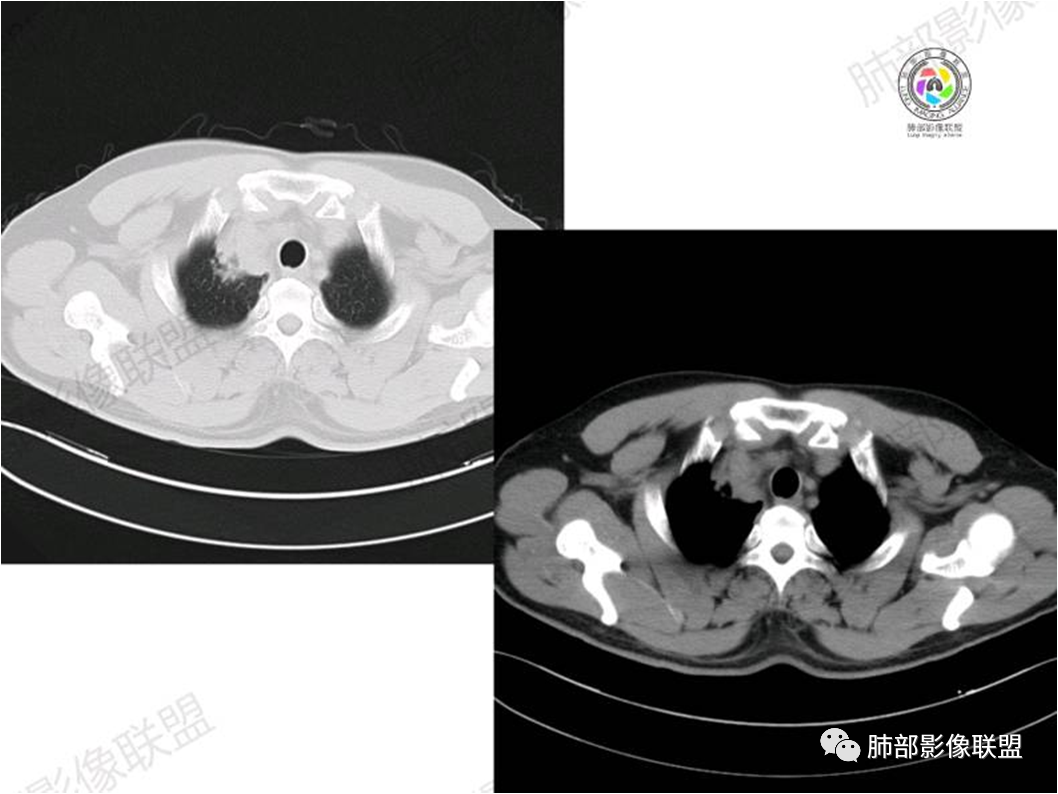

胸部CT:

病灶紧贴纵隔胸膜

糊墙,胸膜外未见明显侵犯迹象

病灶整体狭长一些

边缘平直、凹陷为主

支气管外侧带的通畅,片内侧带的似乎中近端狭窄,堵塞

内部肺动脉走形还可以

近端支气管壁弥漫增厚

强化均匀

整体炎性的特点比较明显